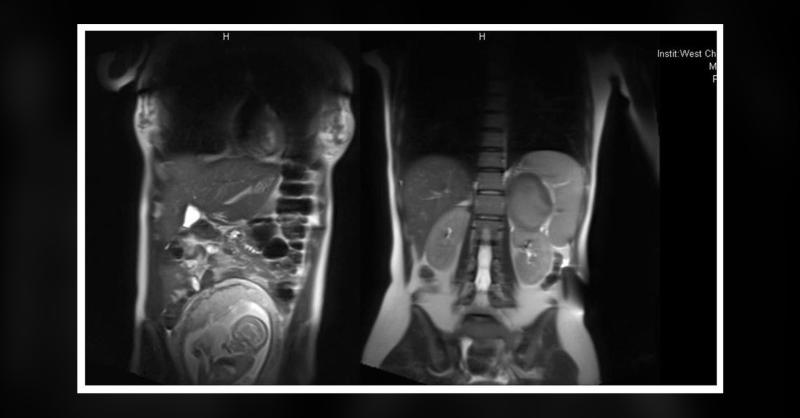

A 28-year-old woman arrived with abdominal striae and irregular glycemic levels at 31 weeks of pregnancy. She was hospitalized due to gestational diabetes mellitus (GDM) and suspected Cushing’s syndrome (CS) during pregnancy. In her physical assessment, her blood pressure registered at 132/80 mmHg. She displayed physical traits including a rounded